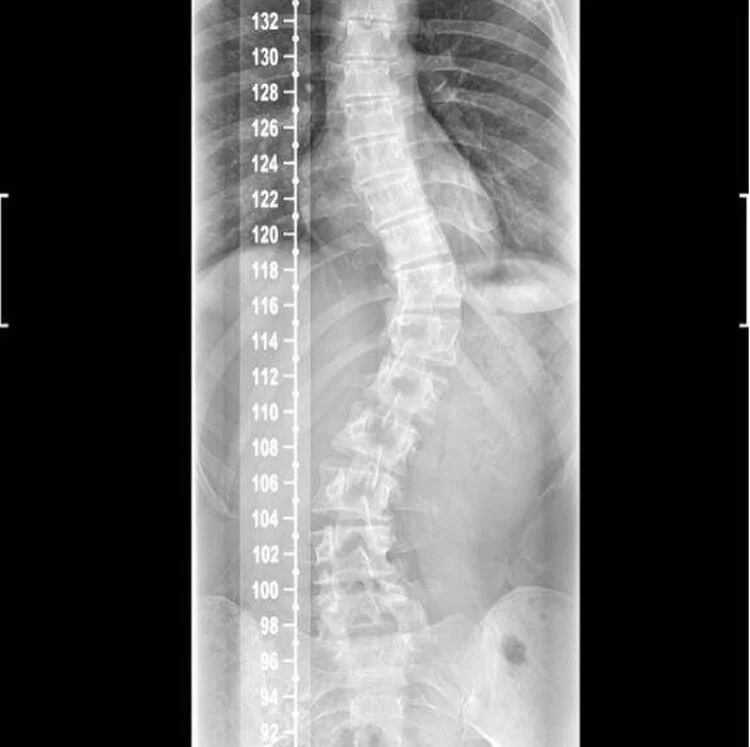

During sixth form, I was diagnosed with scoliosis – (swipe to see my scan lol). I was told by my doctor that it’ll probably get worse throughout my life. It gives me pain for most of the day, so it isn’t really something I can forget about. I felt disgusting, unattractive and like I didn’t belong in my own skin. Thus began my terrible body dysmorphia.

In second term, I got a back brace in an effort to correct my spine, and it was one of the worst decisions I ever made. The brace was bulky, painful, and I felt too ashamed to leave the house in it. I missed so many lectures, and I couldn’t even concentrate when I was copying up the notes at home because of the pain. I could hardly breath, and eating anything made me uncomfortably full (not great for a bulimic). I couldn’t be in the same room as people when I was wearing it, and didn’t let my parents even look at me when it was on. I developed a fear of being touched by people, and that extended to when I wasn’t wearing the brace too. I started meticulously tracking my calories in an effort to regain control. I never wanted the shameful feeling that came with being sick, so to combat this I made sure I kept within my calories. A hair over, and I’d have a meltdown. I’d even weigh lettuce. I was so paranoid around food, and my relationship with my parents was suffering. I didn’t want to be honest with them because I thought they’d think I was a failure. Eventually I told them and they brilliant with it, despite it being such a confusing thing (love you mum and dad). That whole summer after second year I was extremely depressed, wearing the brace, scared of being touched by my loved ones, and didn’t even have the will power to watch Netflix.

Fast forward to 5 weeks ago, I went on medication. And fuck me it’s incredible. I still have SO much to work on, and often make myself sick, but so much less than before, and I haven’t been paralysed by the fear of food in all that time. My back still hurts, and my imbalances still make me physically weaker in the gym, but I finally feel like there is light at the end of the tunnel. For the first time ever, I’m in a calorie surplus, finally giving my body the energy it needs for the GAINZ. George asked me to write something for his page when he started it, and until now I’ve been too afraid. Afraid that people will think I’m a freak, unattractive or a selfish diva. But I have a mental health condition that has manifested itself through food, and I shouldn’t bend to it’s will any more, or feel ashamed. I’ve spoken to so many people and they’ve told me they have similar issues with food, so why are we all hiding? It’s time we all showed some more compassion to ourselves.